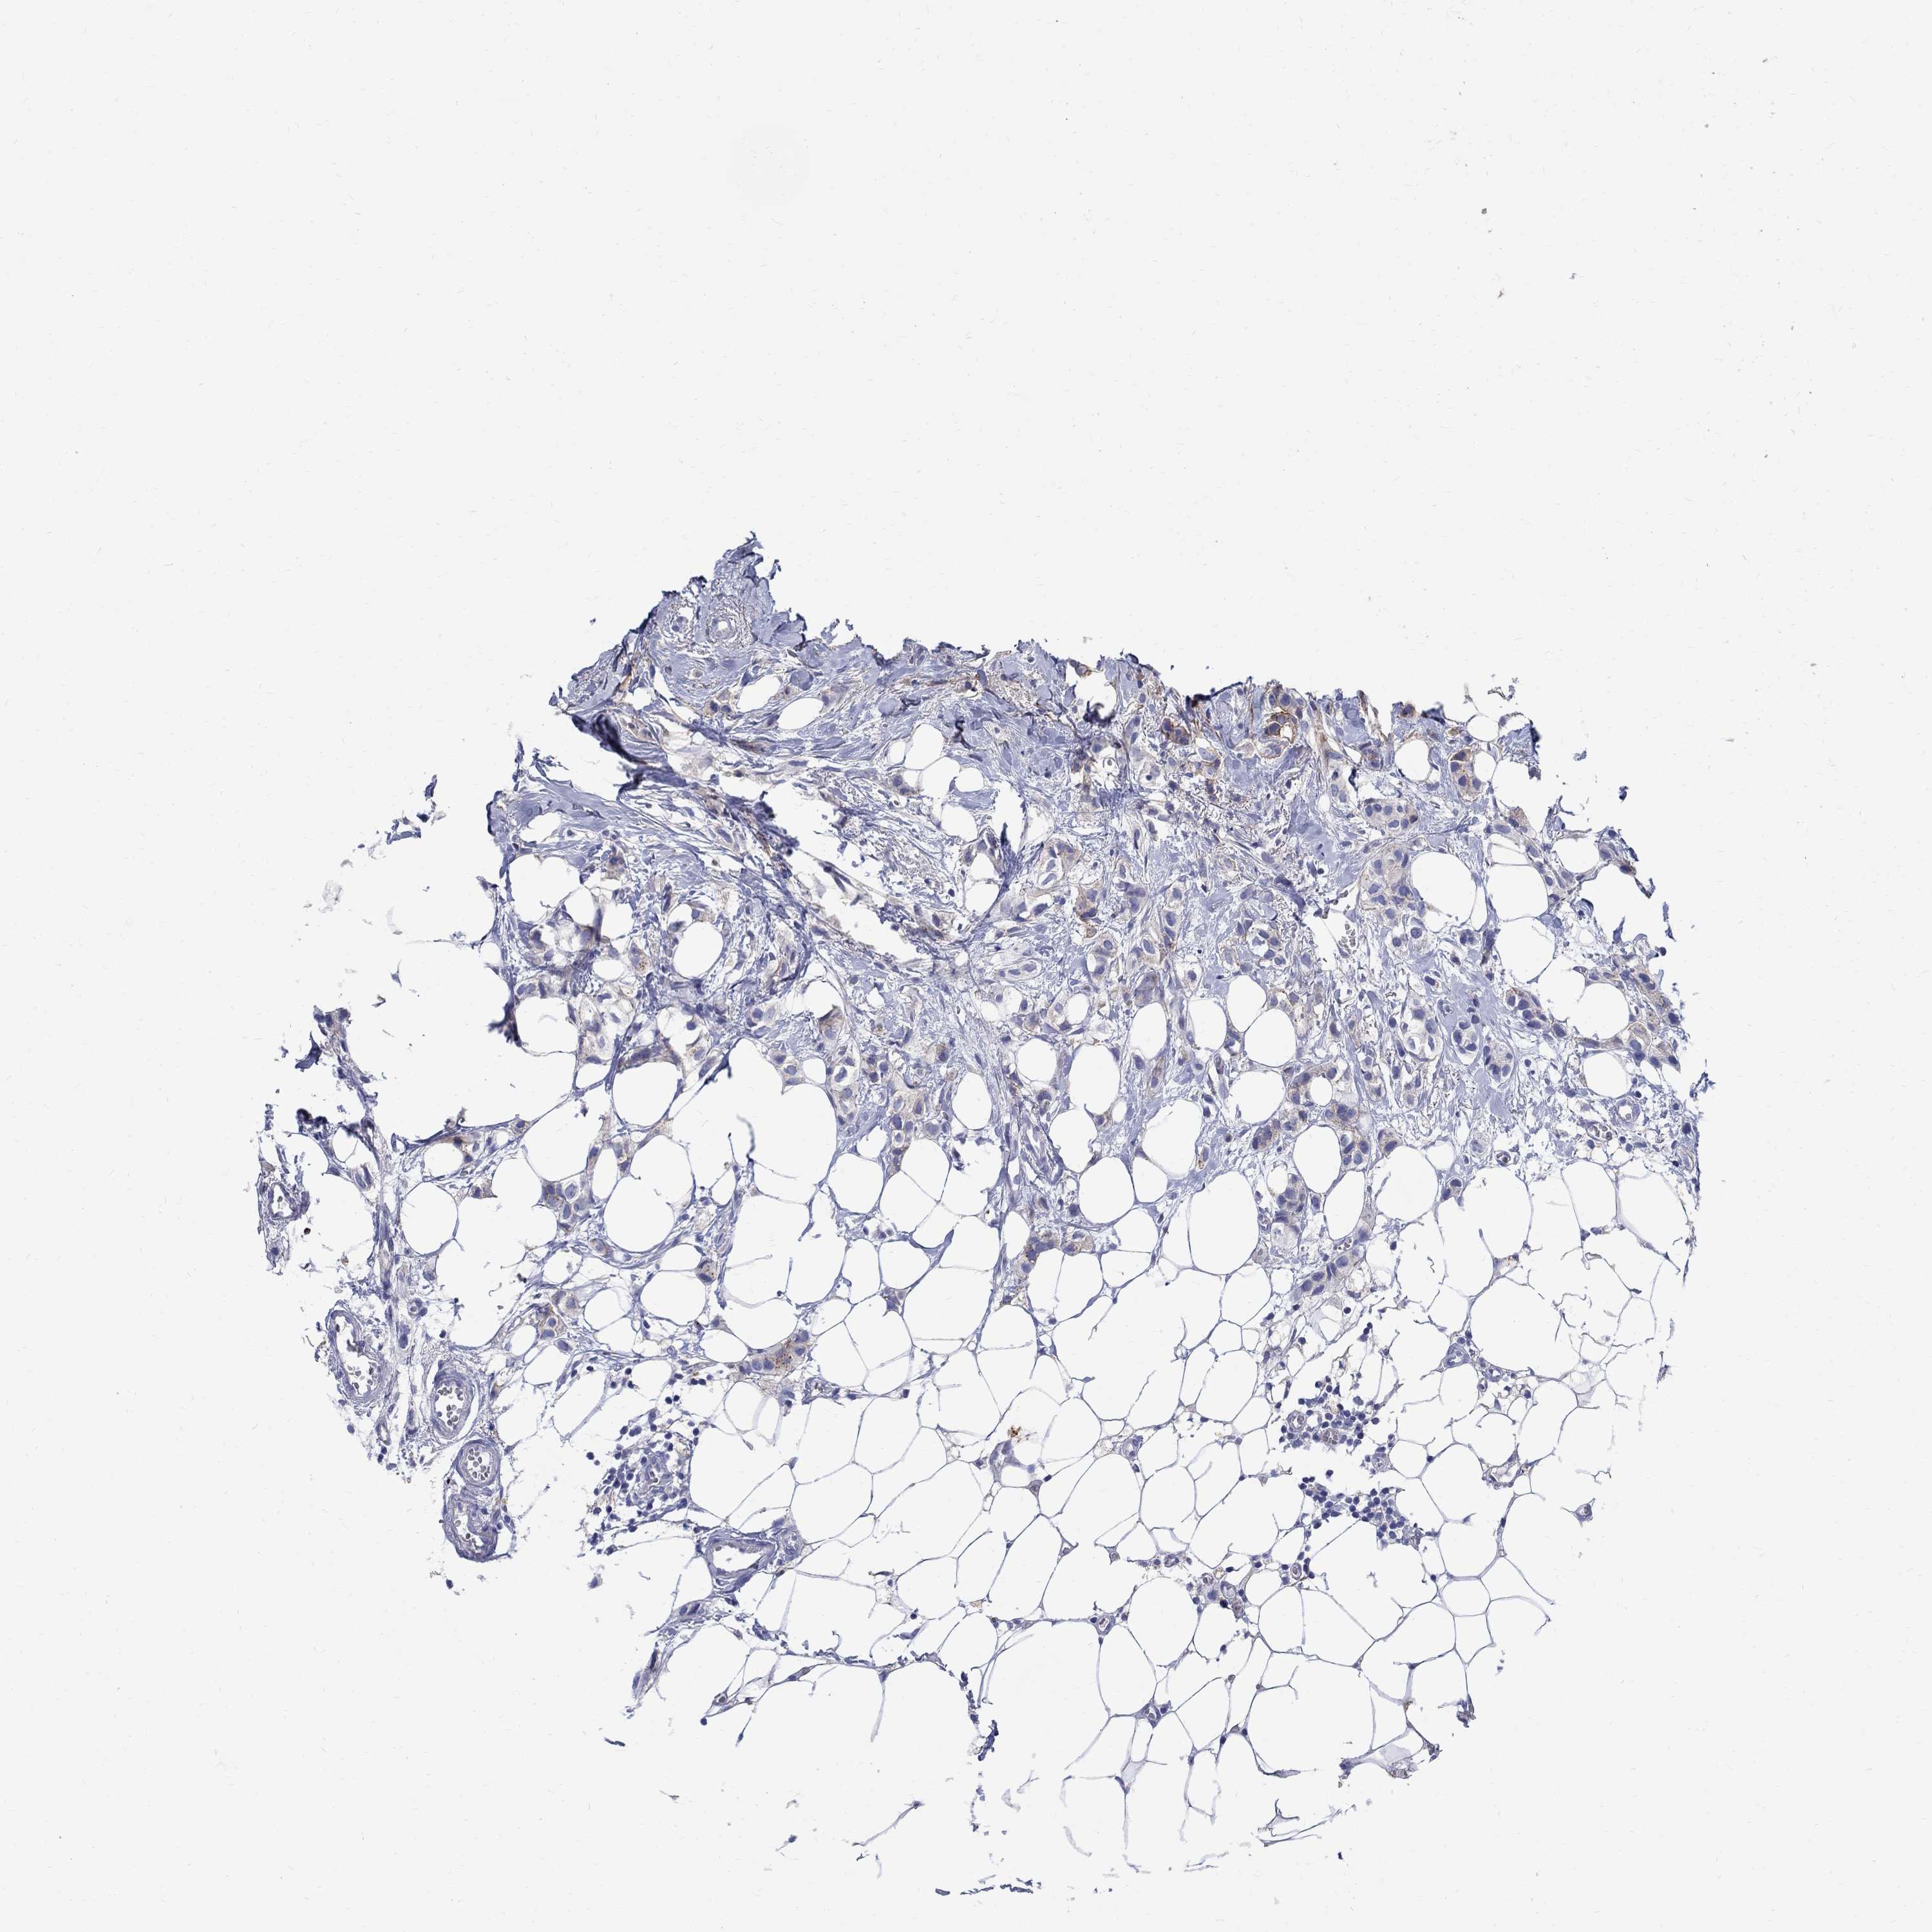

BRCA TCGA BRCA VALIDATION PROTEIN EXPRESSION

ANTIBODIES

AND

VALIDATION